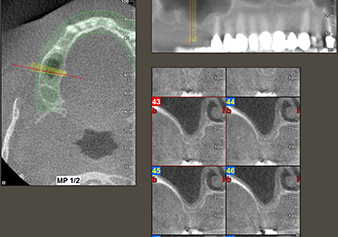

A 49-year-old female patient, a non-smoker and with nothing remarkable in her general medical history, was referred to our oral surgery practice for surgical extraction of tooth 16 and subsequent implantation. After the extraction, the patient experienced mild sinusitis trouble with the resultthat we initially waited six months before carrying out the measure. The residual bone height at the planned implant position measured 3-4 mm (Fig. 1 and 2).

The I2A instrument (diameter 2.0 mm) was then used to perforate the sinus floor intermittently and on the smallest scale possible. This special piezosurgical method ensures that the Schneiderian membrane is not damaged. When the Z25P was used, the membrane was already lifted slightly by the coolant supplied via the instrument tip (Fig. 3). The coolant quantity was just 50% in order to avoid high pressure in the implant bed.

Following an intermediate check (Fig. 4) a further preparation step was performed (Fig. 5). Afterwards, the hydraulic Z35P instrument was used to lift the membrane to the desired position (Fig. 6 and 7). This was followed by further piezosurgical preparation of the implant bed, concluded with a rotary bur and shoulder milling cutter up to the implant diameter of 4.8 mm. Before the implant was inserted, the augmentation material (particle size approx. 0.8-1.6 mm) was introduced underneath the Schneiderian membrane (Fig. 8).